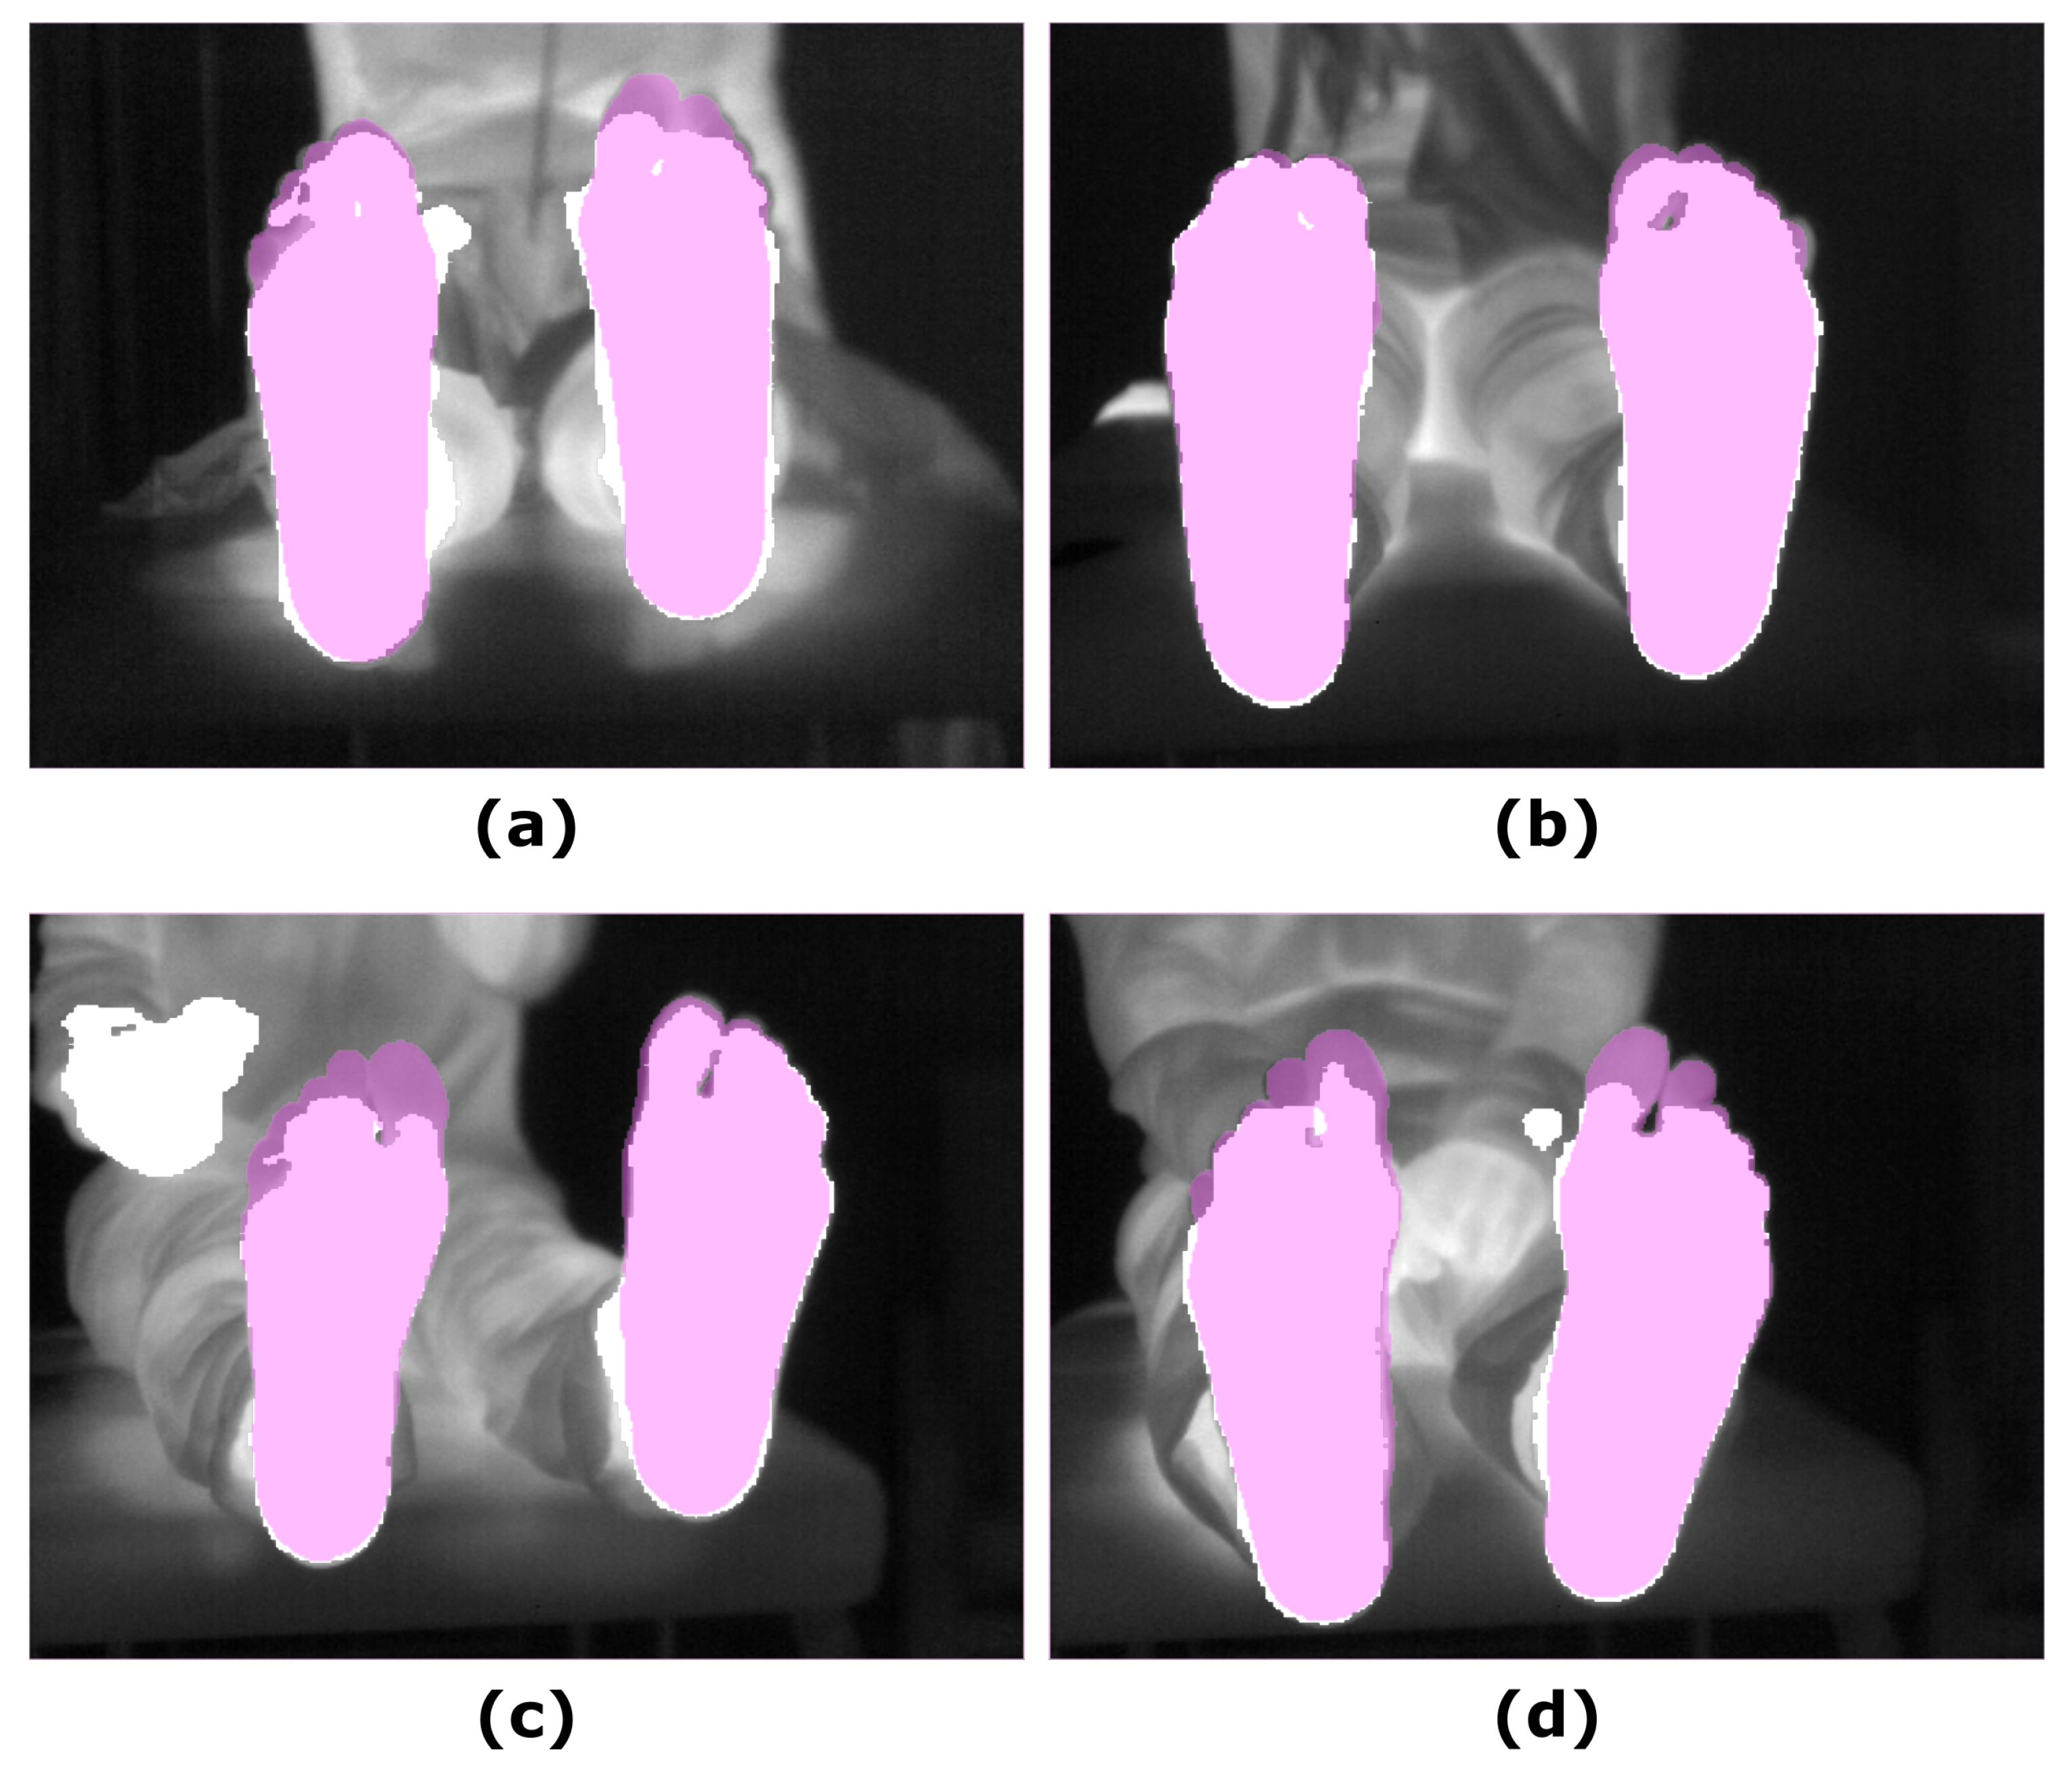

The overlap measures for the SegNet segmentation approach, in which IR images were employed as input, are summarized in Table 4, according to the parameter in Equation (1). The best performance, according to the overlap measures, was achieved for an value equal to one. For illustrative purposes, Figure 4 displays the final predictions according to the varying parameter.

Figure 4.

Illustrative example showing the final prediction for the SegNet approach according to the parameter in Equation (1): (a) IR input image; (b) Final prediction = 0; (c) Final prediction = 0.2; (d) Final prediction = 0.4; (e) Final prediction = 0.6; (f) Final prediction = 0.8; (g) Final prediction = 1. The ground truth (pink mask) was overlapped to both, the IR image and the corresponding final predictions (white mask).

Similar to that observed for the other segmentation approaches, no significant changes were found for the overlap measures in the corresponding final prediction according to the time point. Regarding intergroup differences, in comparison to the approaches based and refined employing the RGB-D images, particularly the UPD, the DICE and IoU coefficients were significant lower at T0 (p < 0.05) but not at T5 (p < 0.05). Figure 5 shows the final prediction, based on the IR images, for four different subjects, corresponding to the best and the worst overlap measures (DICE), at T0 and T5.